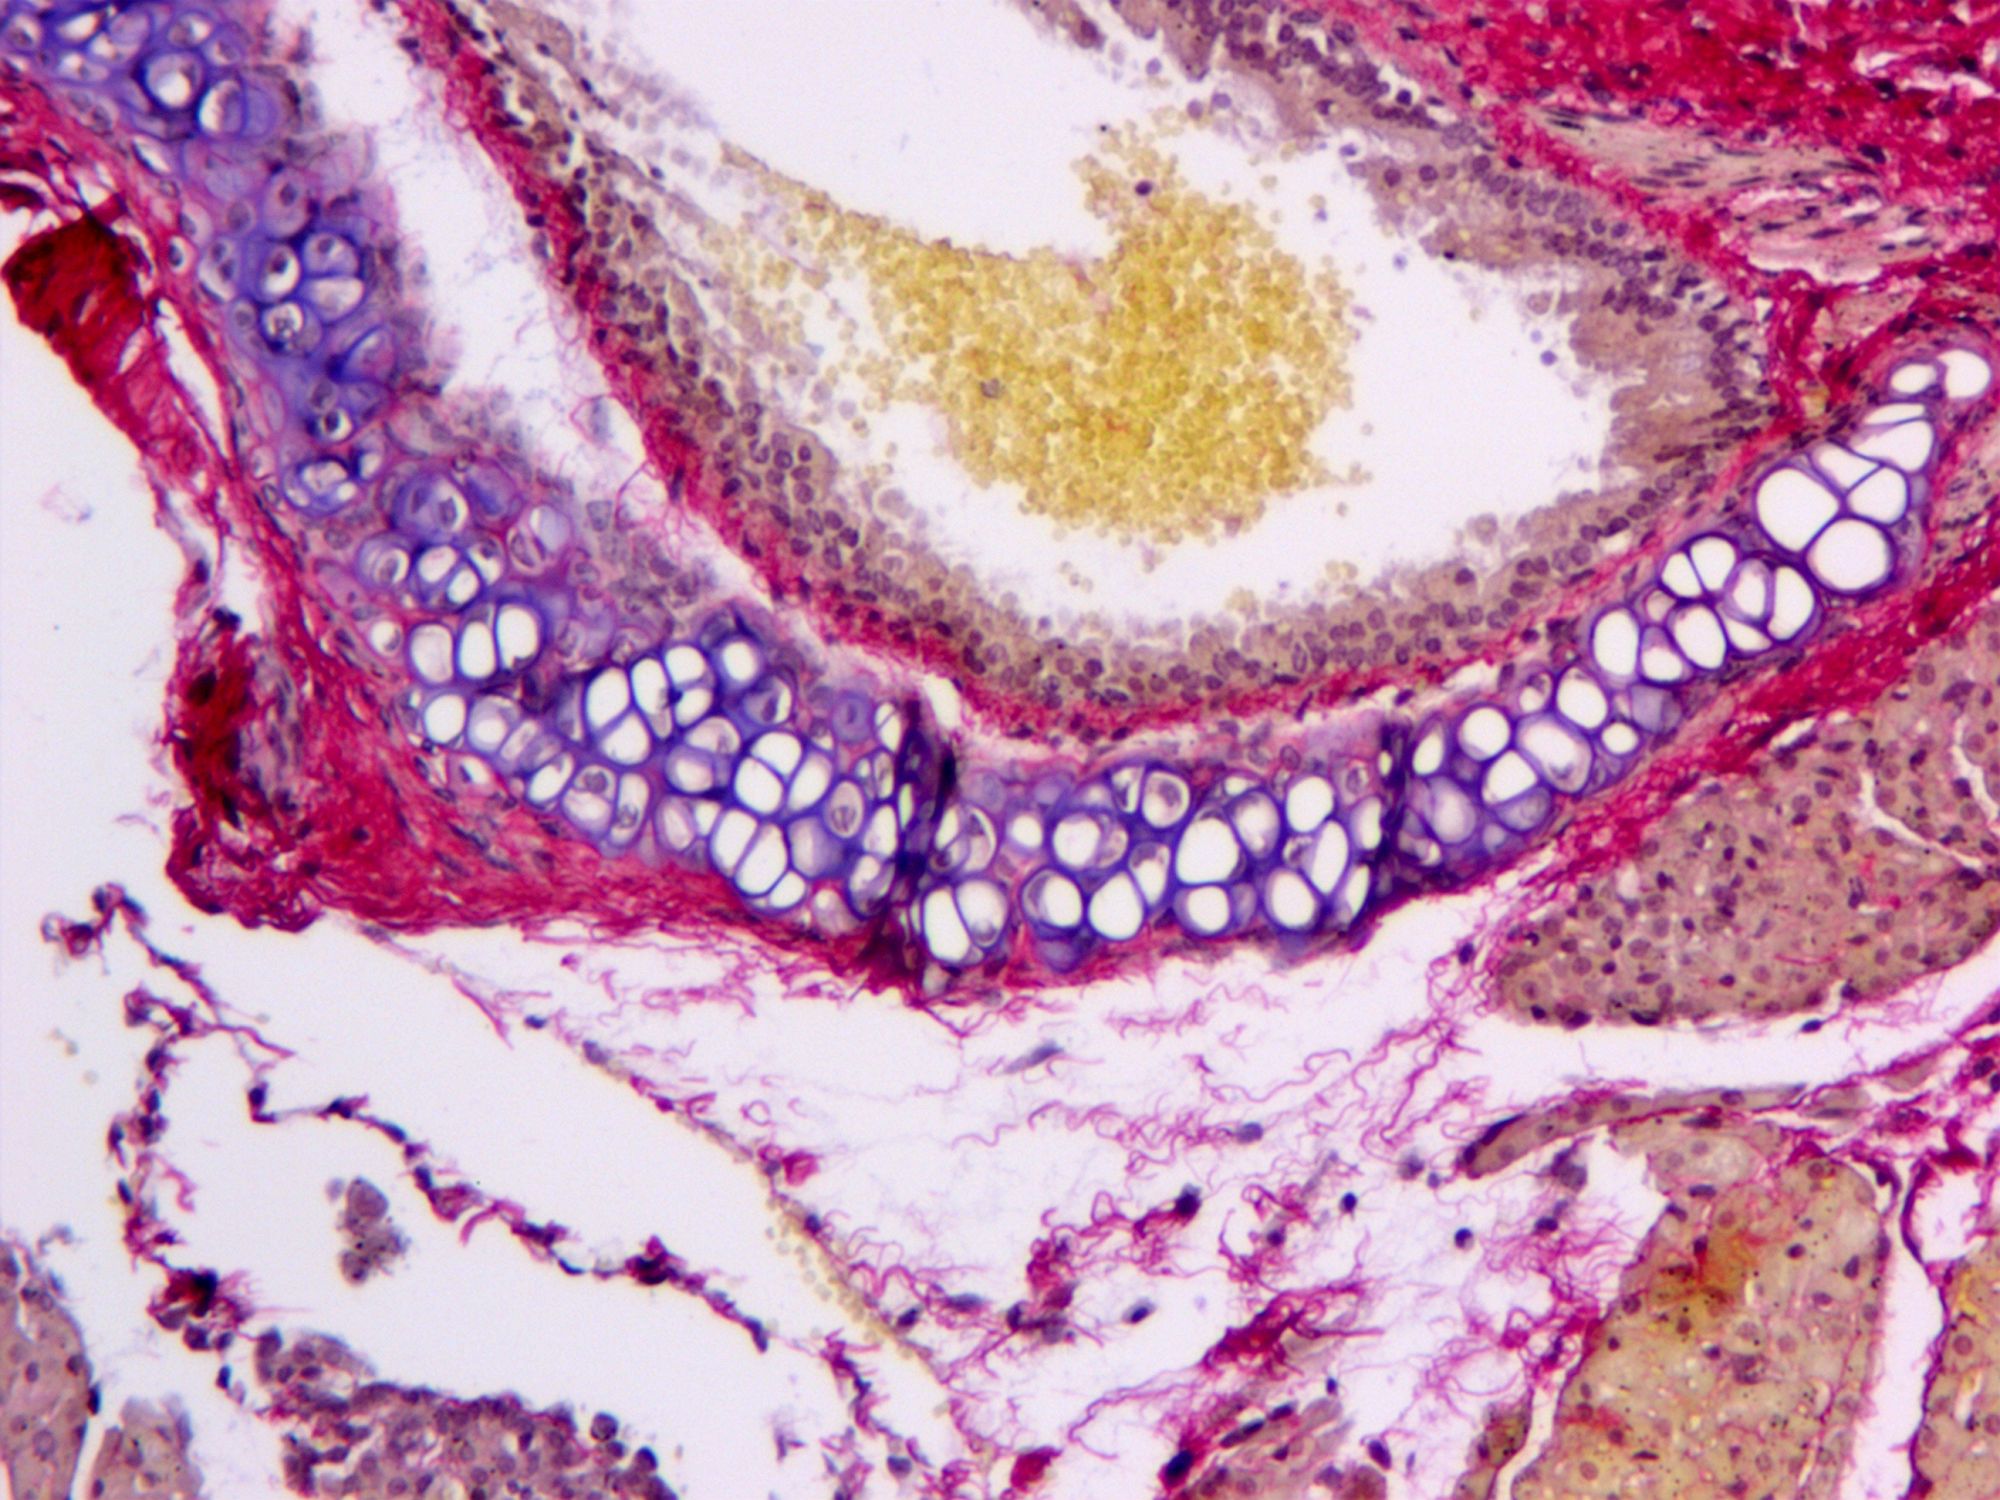

MASSON染色實(shí)驗(yàn)的目的是為了在組織學(xué)研究中可視化并區(qū)分不同類型的纖維,特別是膠原纖維和肌纖維。MASSON染色實(shí)驗(yàn)?zāi)康挠?a style='text-decoration: underline;color: rgb(84, 141, 212);' style="text-decoration: underline;color: rgb(84, 141, 212);" href="http://www.jx3dscan.com/shiyan/view/heranse.html" target="_self">普拉特澤生物病理染色平臺(tái)總結(jié)分享,病理組織染色平臺(tái)為廣大科研實(shí)驗(yàn)人員提供MASSON染色實(shí)驗(yàn)服務(wù),先一起來學(xué)習(xí)學(xué)習(xí)關(guān)于MASSON染色實(shí)驗(yàn)?zāi)康?/strong>

這種染色方法通過特定的化學(xué)反應(yīng)和染料選擇,使得不同類型的纖維在顯微鏡下呈現(xiàn)出不同的顏色,從而便于研究者對(duì)組織結(jié)構(gòu)和病變進(jìn)行準(zhǔn)確的觀察和分析。

㈠:MASSON染色通過特定的染色劑:能夠使膠原纖維和肌纖維分別呈現(xiàn)出不同的顏色,從而實(shí)現(xiàn)對(duì)這兩種重要組織成分的精準(zhǔn)區(qū)分。這對(duì)于后續(xù)的組織學(xué)研究具有非常重要的意義。

㈡展示組織纖維化程度:作為一種重要的組織纖維化觀察方法,MASSON染色能夠清晰地顯示出組織中的纖維結(jié)構(gòu),包括膠原纖維的排列、形態(tài)和數(shù)量等。通過對(duì)這些信息的觀察和分析,研究人員可以準(zhǔn)確地評(píng)估組織的纖維化程度,為進(jìn)一步的研究和治療提供重要依據(jù)。

㈢揭示病變過程:MASSON染色在病理學(xué)研究中具有廣泛的應(yīng)用價(jià)值。通過對(duì)病變組織的染色和觀察,研究人員可以更加深入地了解病變過程中膠原纖維和肌纖維的變化情況,從而為疾病的診斷和治療提供有力支持。